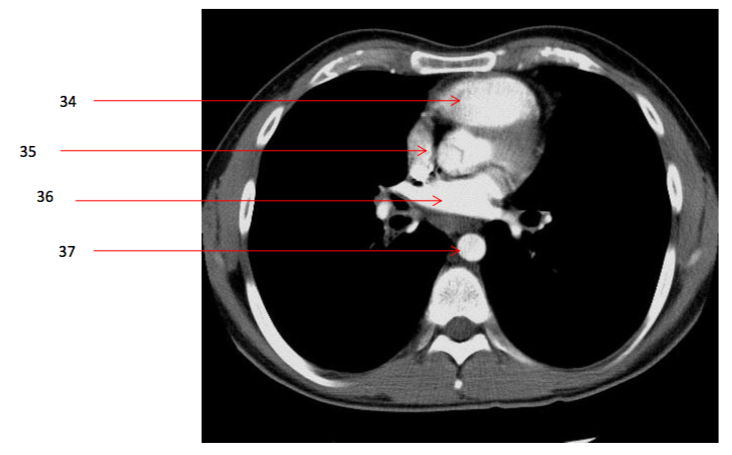

Number 34?

Rt ventricle

35

Number 32?

Left Atrium

36

Number 30?

37

Number 42?

Number 37?

decending thoracic aorta

Number 35?

Rt atrium